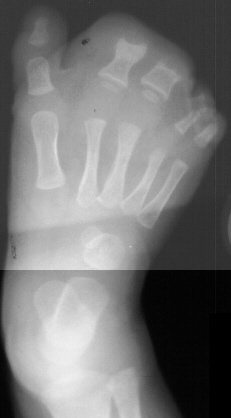

of right foot, at age 5 years, she underwent partial amputation of the

right 2nd and 3rd metatarsals(images 3 & 4). Now at age 10, she has

been doing well, participating in all sports. She has noted that there

has been some difficulty in finding shoes that fits but does not complain

of any pain.